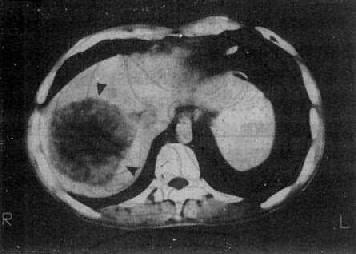

图4-3-5 原发性肝癌

CT增强扫描,肝右叶有一较大圆形低密度肿块(↓),其边缘

部可见多个较密度的强化结节,其强化程度不如正常肝,中

心部仍为未强化的低密度区